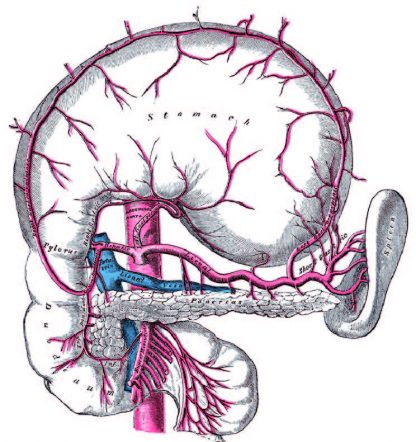

von 1810)

und der Nieren

Darm – Dünndarm – Dickdarm